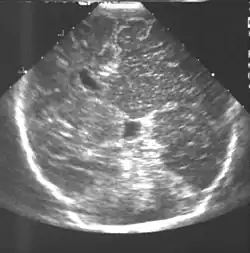

Die Diagnose kann bereits frühzeitig mittels Sonografie[8], sonst mittels Magnetresonanztomographie oder Computertomographie gestellt werden. Dabei finden sich neben der abschnittsweisen Vergrößerung Zeichen der kortikalen Dysplasie, Pachygyrie, Heterotopie und Gliosen.[7][9]